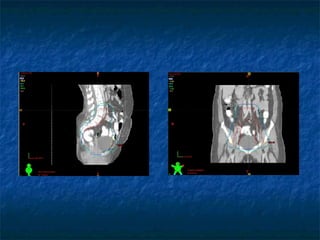

IMAGING For treatment planning purposes orthogonal radiographs/CT images are taken Images are transferred to Treatment planning system. If radiographs are to be used for planning then radiographs are scanned to transfer images to TPS. Catheter reconstruction done on TPS

IMAGING For treatmentplanning purposes orthogonal radiographs/CT images are taken Images are transferred to Treatment planning system. If radiographs are to be used for planning then radiographs are scanned to transfer images to TPS. Catheter reconstruction done on TPS